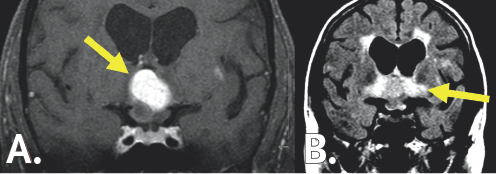

A minimally invasive, right trans-ventricular, trans-choroidal fissure approach was selected for definitive treatment. In the procedure, Dr. Forbes advanced a small tubular retractor into the ventricular system. The choroidal fissure, or the natural cleft between the fornix and thalamus, was gently opened—providing access to the third ventricle. Under high magnification, the tumor was meticulously removed. Following surgery, MRI demonstrated appropriate resection of the tumor with complete resolution of tumor-associated inflammation in the hypothalamus and optic tracts (Figure 9.2). The physical therapy team helped Anne speed through her recovery. All visual symptoms had resolved within a few days. Anne had noted marked improvement in short-term memory only a few weeks following the surgery. Three months after the surgery, Anne had regained her old form at Sudoku and resumed all of her old hobbies. In the months ahead, Anne would recover the high quality of life she enjoyed prior to the tumor and even find time to crochet a doll for Dr. Forbes and the neuro-surgery team.

(Left top) A white blob is in the center of the figure. It is surrounded by gray colored variations contained within a black and dark gray boarder. (Right top) A yellow arrow points to a dark gray colored blob in the center of the image. It is surround by gray colored variation. (Left bottom) A white colored region resembling an 'X' surrounds a black butterfly-looking structure. It is surrounded by light gray coloration which is contained within a black and white boarder. (Right bottom) A yellow arrow points to a slightly darker gray region than the surrounding light gray coloration. It is surrounded by a black and white outline.

FIGURE 9.2 Post-operative MRI. MRI (A) imaging pre- (left) and post- (right) operatively. The yellow arrow points to the third ventricle after the brightly appearing tumor was removed. The optic apparatus, seen below the third ventricle, has returned to normal size following tumor removal. MRI (B) shows significant improvement in the tissue damage associated with the tumor seen by the bright white signal pre- (left) and post- (right) operatively. The yellow arrow highlights the lack of inflammation in this region after the tumor excision.